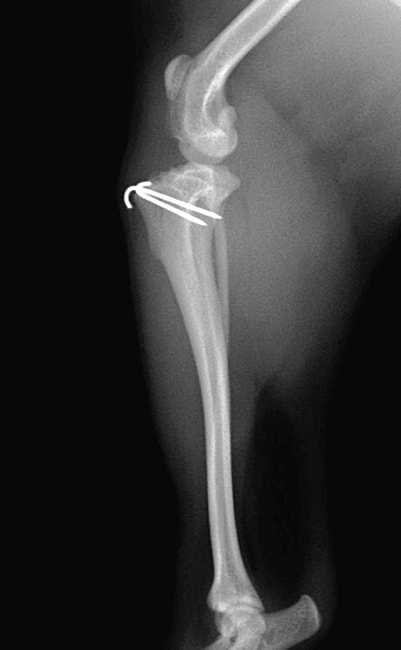

■ 症例22 ポメラニアン 1歳5か月 去勢雄

左後肢の挙上を主訴に来院した。整形学的検査、レントゲン検査より左右の膝蓋骨脱臼(左GradeⅡ〜Ⅲ、右Grade Ⅱ)を認めた。また、脛骨の前方引き出し試験の際に、引き出し兆候は認められないものの、疼痛が認められたため、前十字靭帯の損傷が疑われた。術中における、目視および関節内の操作によって、前十字靭帯の損傷や過伸展といった異常が認められなかったため、膝蓋骨脱臼の整復のみ実施した。手術手技は縫工筋及び内側広筋の解放、脛骨粗面の外側転位、滑車ブロック形造溝術、内外側関節包の縫縮を実施した。本症例は跛行もなく経過良好である。しかし、頸骨高平部の角度(TPA)が 右26.2°、左24.9°であり、解剖学的に前十字靭帯損傷のリスクが高いことから今後の経過に注意が必要である。